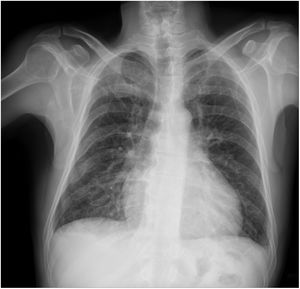

Chest radiography may be useful for assessing the disease in more advanced stages (Figure 1). Cardiomegaly with enlargement of the right and left heart chambers may be observed. However, pulmonary congestion is usually mild or non-existent.50

The Rassi score (Table 2) is used to stratify mortality risk in patients in the chronic phase and with cardiac involvement.99 The variables assessed in the score are gender, low QRS voltage on ECG, nonsustained ventricular tachycardia, global or segmental left ventricular wall motion abnormalities, cardiomegaly on chest X-ray and heart failure (NYHA class III or IV). The score estimates 10-year mortality risk, classifying patients as high risk (12-20 points), intermediate risk (7-11 points) or low risk (0-6 points). In the development and validation cohorts on which the score was based, the 10-year mortality rates for high, intermediate and low risk patients were 84-85%, 37-44% and 9-10%, respectively.99 The presence of nonsustained ventricular tachycardia is associated with a 2.15-fold increased risk of mortality, and the combination of this arrhythmia with left ventricular systolic dysfunction is associated with a 15.1-fold increased risk for subsequent death.100